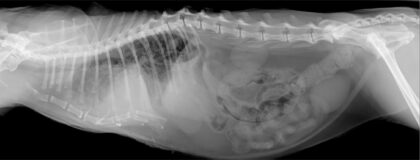

In diesem vetinar lernen Sie die Grundlagen der Röntgenlagerung von Thorax, Abdomen und Kopf. Ziel dieses vetinars ist es, möglichst praxisbezogen mit Beispielen, einen Einblick in die korrekte Röntgenlagerung bei Hund und Katze zu bekommen und auswertbare Röntgenaufnahmen zu erhalten. Lagerung ist der erste wichtige Schritt für eine gute Auswertung und richtige Diagnosestellung.

- OP-Assistenz 8: Röntgenlagerung Abdomen, Thorax, Kopf